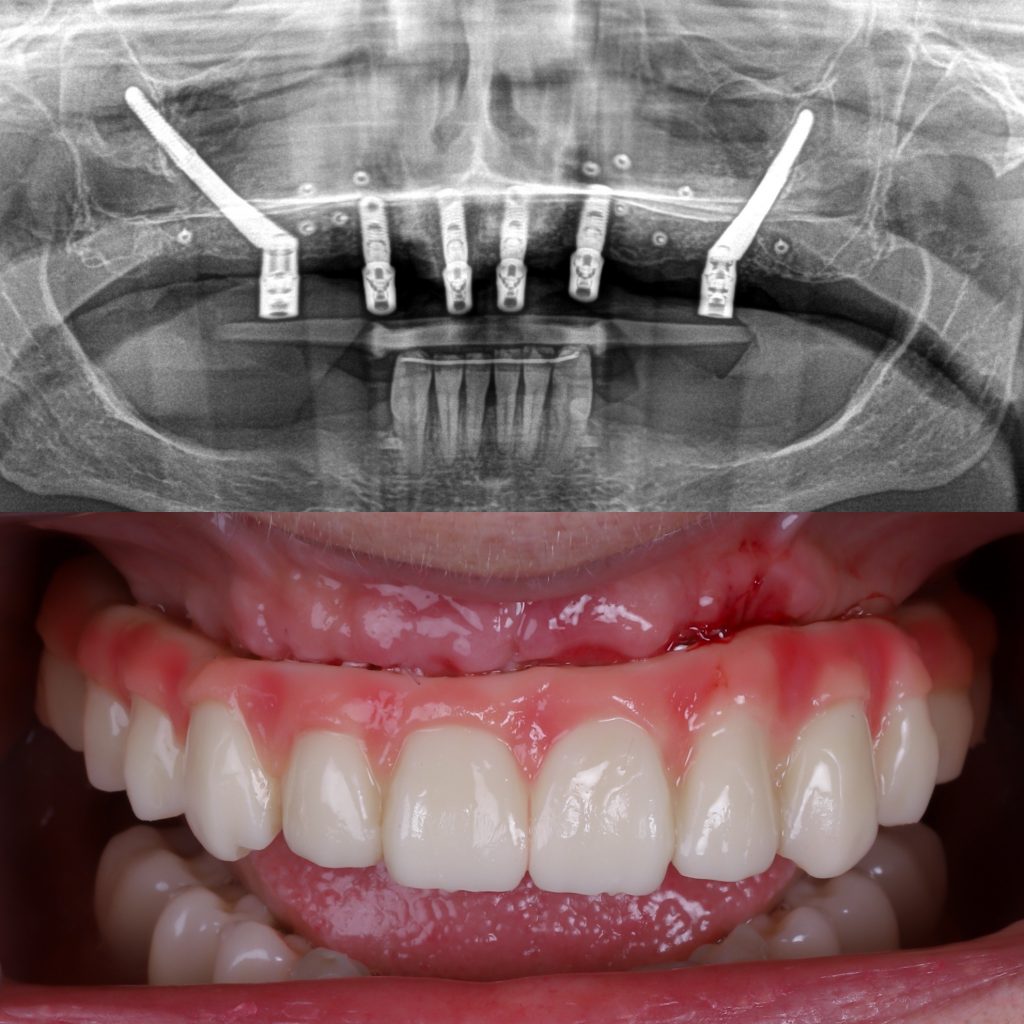

implantes subperiósticos

Son una alternativa en casos con pérdida ósea extrema en los que no es posible introducir un implante dentro del hueso.

En lugar de un tornillo, se diseña una estructura metálica personalizada que se coloca sobre el hueso y bajo la encía.

Se fabrican mediante tecnología digital para que se adapten con precisión a la anatomía del paciente.

Son útiles cuando no es viable realizar injertos o en pacientes que no desean cirugías reconstructivas extensas.